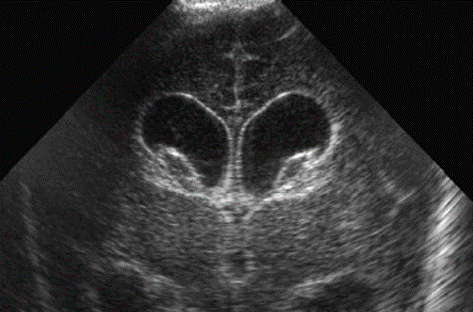

Neonatology Grade 2 IVH Pitfall 2 Image